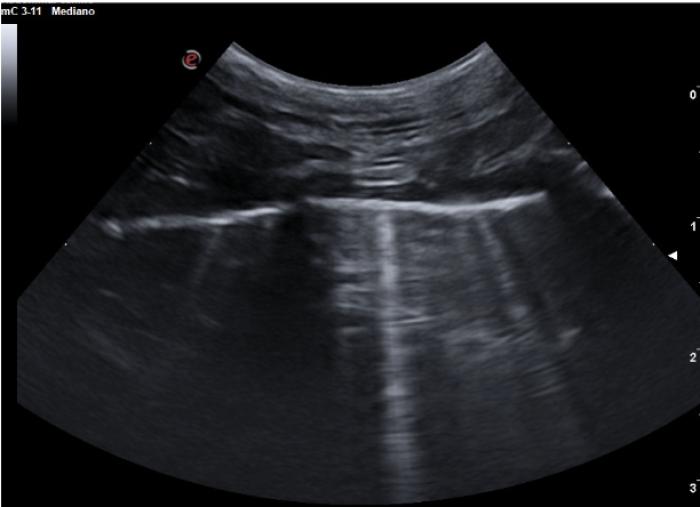

Comenzaremos posicionando el transductor perpendicular a las costillas en uno de los espacios intercostales, pudiendo evaluar al menos el espacio entre dos costillas, la línea PP y no más de 2-3 cm de profundidad de campo (Figura 1A-B).

Son visibles en todo pulmón bien ventilado, pero también estarán presentes en el neumotórax por lo que en este punto es vital observar el deslizamiento de la LP para su diferenciación (Figura 3A-B).